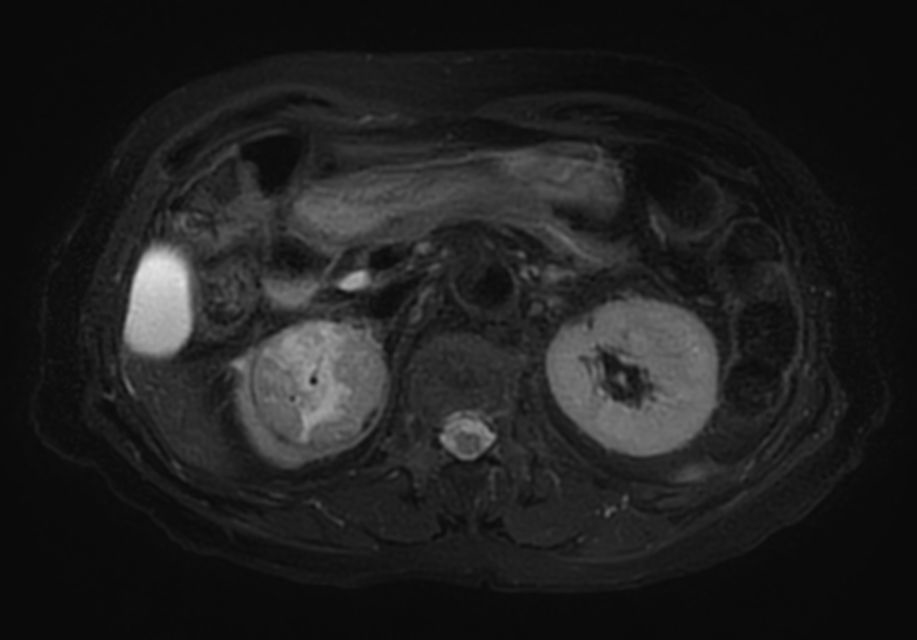

Patient with renal failure. ExamCard includes MultiVane XD to acquire motion-free diagnostic images and 4D FreeBreathing to perform multi-phase contrast-enhanced MRI studies.

T2w SPIR MultiVane XD - Free Breathing